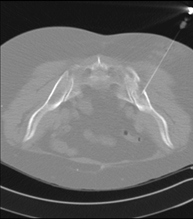

- PAAF (Punción) Tórax guiada por TC

Prueba que consiste en obtener una muestra de tejido de lesiones torácicas, como por ejemplo masas pulmonares, mediastínicas, lesiones óseas, etc. Para ello se administra anestesia local sobre la zona de la punción, la cual se realiza con agujas de fino calibre. Todo el procedimiento se realiza controlado por imágenes obtenidas por Tomografía Computarizada (TC) en varios momentos de la punción, mediante un equipo de Fluoroscopia-TC. Tras la prueba, el paciente permanece unas horas hospitalizado. Es necesario aportar pruebas de coagulación antes de la punción.